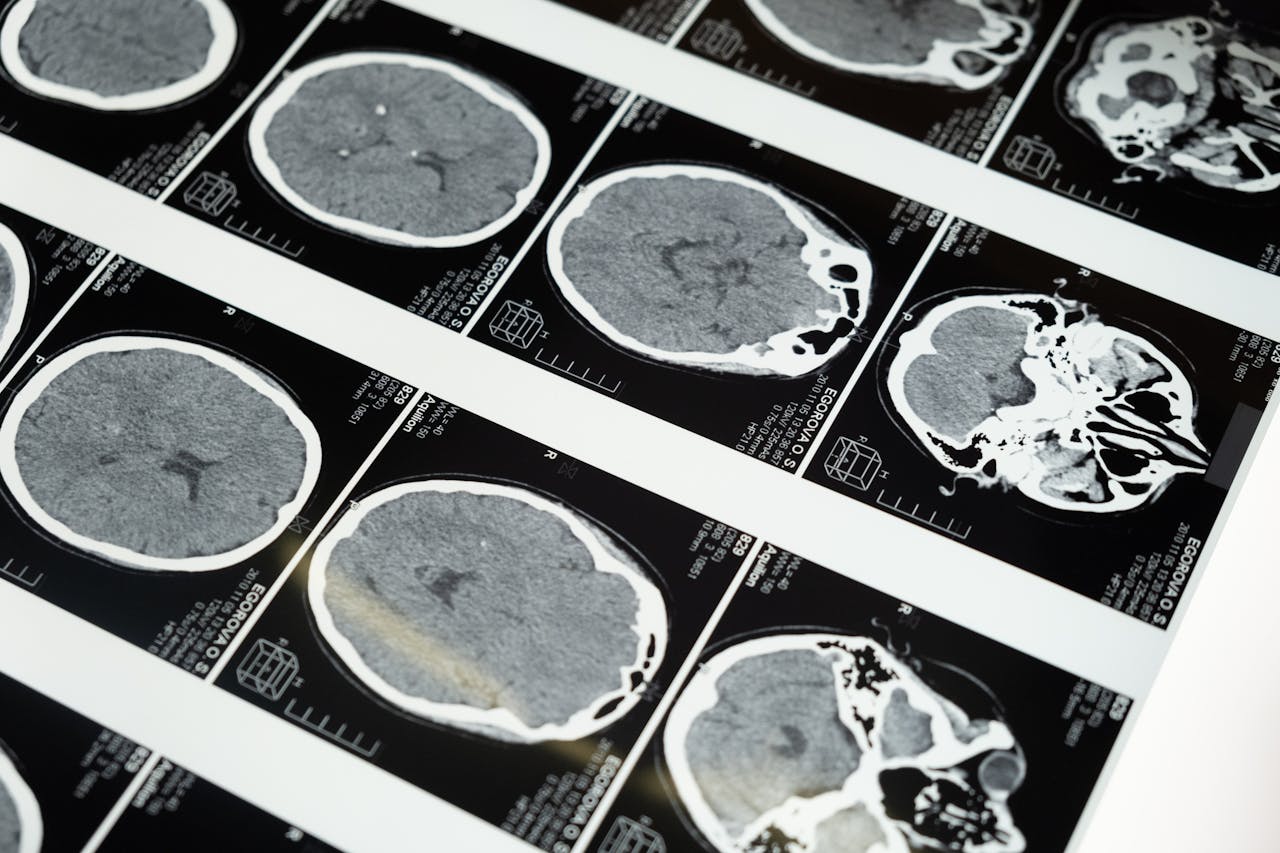

The Role of Neurosurgeons in Treating Traumatic Brain Injuries

Traumatic brain injuries (TBIs) are among the most serious medical conditions that can result from accidents, falls, or sports-related impacts. Neurosurgeons play a crucial role in treating these injuries, helping